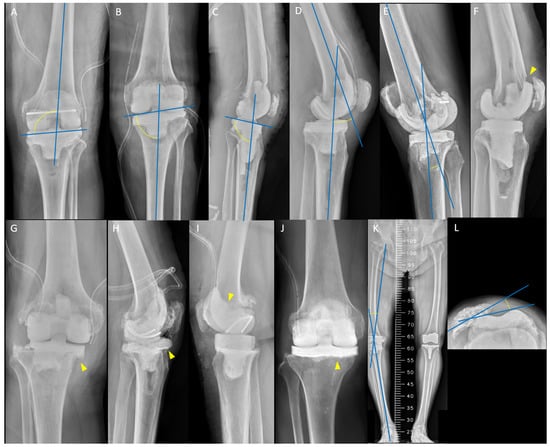

There were 40 (19.7%) mechanical complications in 203 spacers. The ICC value for mechanical complications was 0.974 (range, 0.918 to 0.990; p < 0.001). The outcomes of spacer placement performed by HV or LV surgeons are presented in Table 2. The overall mechanical complication rate was lower in HV surgeons (3.8%) than in LV surgeons (36.7%) (p < 0.001), especially for joint subluxation or dislocation. The overall reoperation rate was lower in HV surgeons (0.9%) than in LV surgeons (24.5%) (p < 0.001), especially in spacer exchanges (Figure 4A–F). Among the cases that had 36 mechanical complications in LV surgeons, 66.7% (24/36) underwent reoperation, and 91.7% (22/24) of the reoperation procedures were spacer exchanges. There were 1 (0.9%) and 4 (4.1%) knees that had unexpected early reimplantation that were performed smoothly after mechanical complications by HV and LV surgeons, respectively (Figure 4G–I). Table 3 presents the details of these mechanical complications, in which all mechanisms were atraumatic and 92.5% had early failure (≤6 weeks) after spacer insertion. All knees requiring reoperation were treated with hinge braces and were free of instability before reimplantation.

Figure 4. Examples of mechanical complication: (A) a 68-year-old man after resection arthroplasty (RA) with varus malalignment of tibial spacer (medial proximal tibial angle, 83°); (B) periprosthetic tibial fracture (arrowhead) 3 weeks after spacer insertion; (C) reoperation with tibial spacer exchange; (D) a 63-year-old man after RA with recurvatum deformity (12°); (E) femoral spacer fracture (arrowhead) 4 weeks after spacer insertion; (F) reoperation with both spacers exchange; (G) a 76-year-old woman after RA with tibial spacer without cement stem extension; (H) tibial spacer migration (arrowhead) 6 weeks after spacer insertion; and (I) unexpected early reimplantation smoothly.